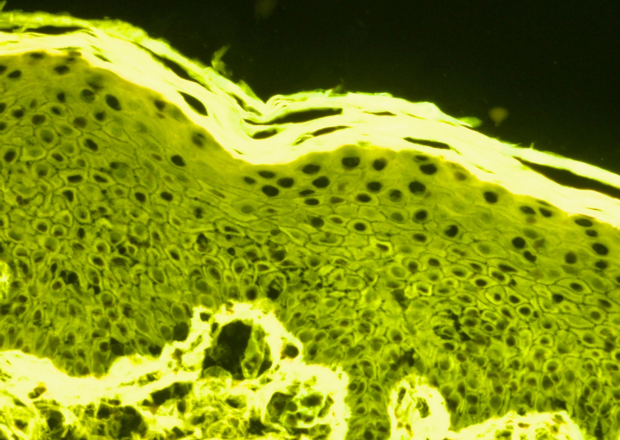

Palga plays a major role in making data available to researchers. Every year, we receive nearly 200 new requests from researchers looking for pathology data and tissue samples, as Palga is able to provide unique insights not available anywhere else in the world. Facilitating scientific research contributes to better treatment plans for patients and improves the quality of care.

The Palga Foundation is proud of its impact on the scientific field, both through the studies in which we are directly involved and the publications made possible by our data. The number of publications we facilitate increases every year.